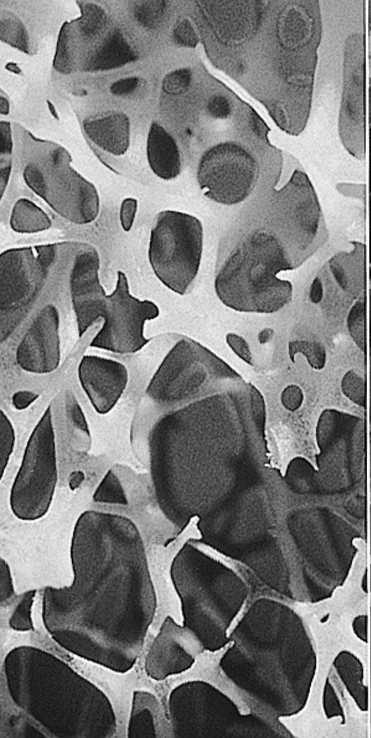

Creation of a fine level model of bone; Estimatingstrength of bone as a function of direction and forces: